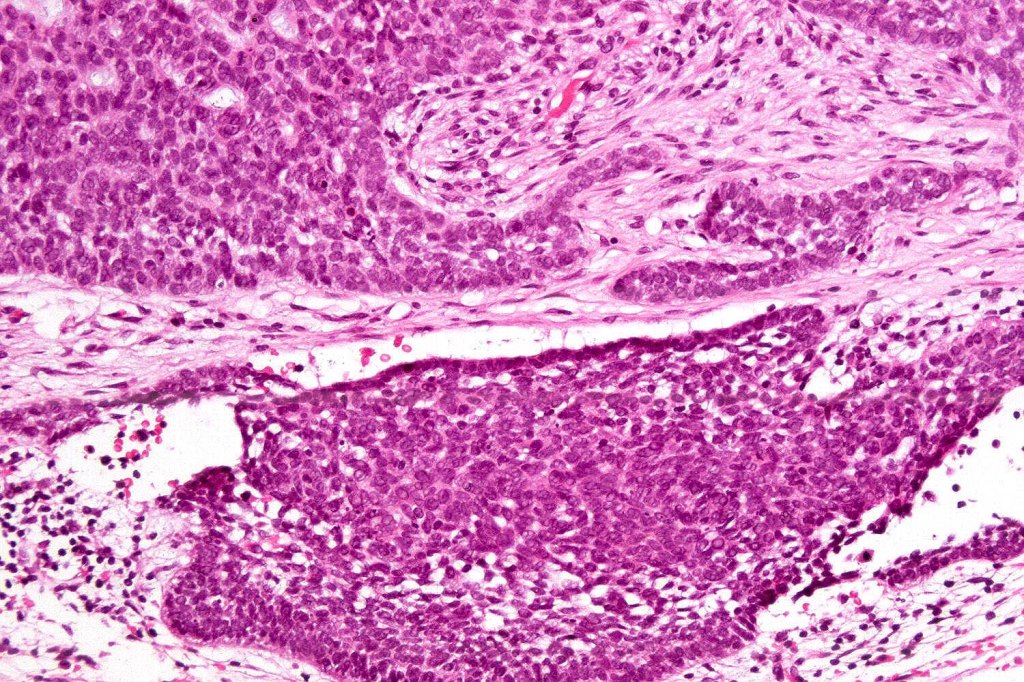

Carcinosarcoma

Cutaneous carcinosarcoma (metaplastic carcinoma, carcinoma with heterologous differentiation)

Histological features

•Osteoid

•Chondroid

•Smooth muscle

•MFH-like features with osteoclasts

•Neural differentiation